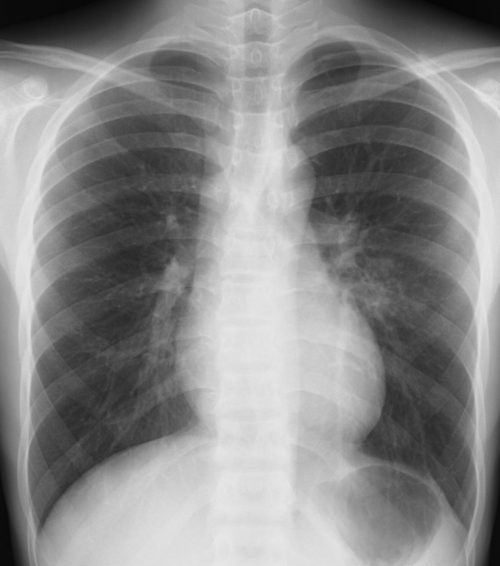

外来でよくみられる肺炎、マイコ・クラミジア・肺炎球菌・ウイルス(RSウイルス・hMPV・インフルエンザウイルスA・B)について実際に経験、外来で治癒した症例を提示します。軽症な変化のものが大多数ですが中には重症なものも紛れていて、注意が必要になります。

【マイコプラズマ肺炎】